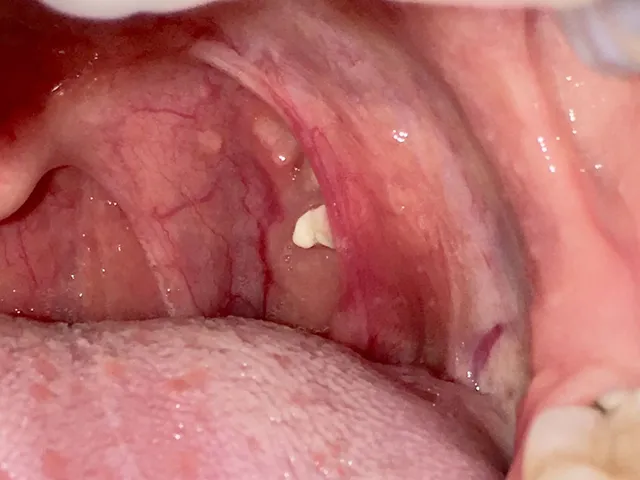

Who gets tonsil stones?

Anyone who has tonsils can get them. However, some people are more likely than others to form tonsil stones, including those who

- have tonsils with lots of indentations and irregular surfaces rather than a smooth surface